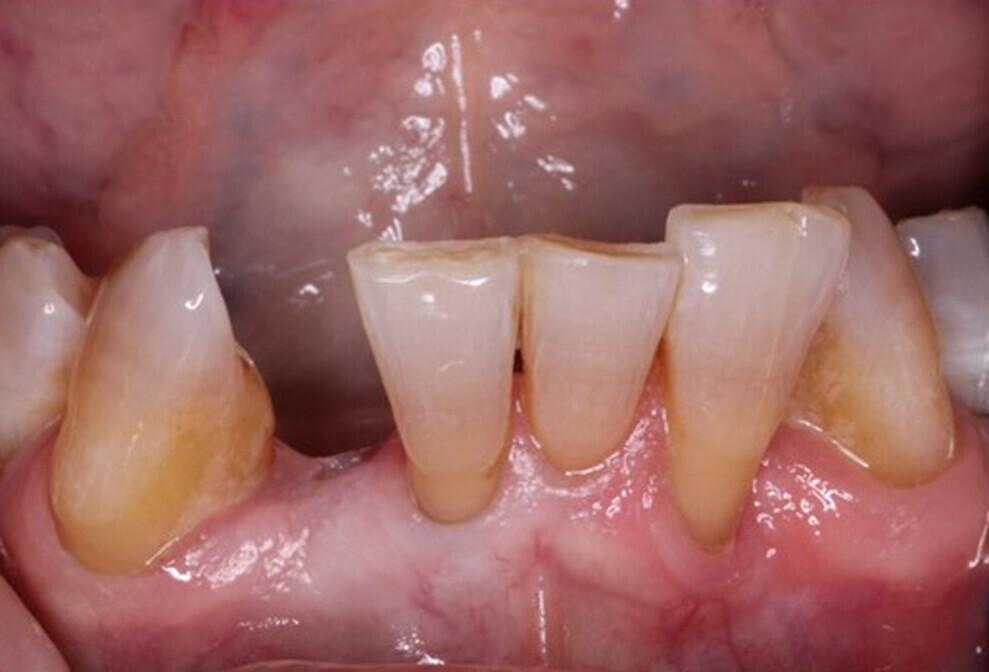

The restorative phase of treatment was initiated after three months of osseointegration. Restoration was completed with a screw-retained crown. A periapical radiograph was taken to confirm seating of the implant restoration on the platform (Fig. 18). Radiographically, it was noted that the bone level on the mesial and distal aspects was at the top of the platform and that there was complete bone fill on the distal aspect of tooth #41. Clinically, the gingiva was healthy and keratinised and presented with no inflammation (Fig. 19).